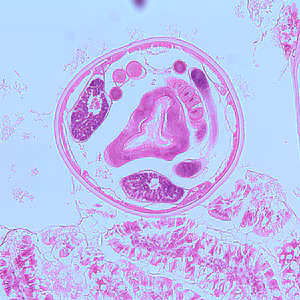

A four-year-old child was admitted to the hospital for sever abdominal pain mimicking appendicitis. A small section of bowel was removed and sent to the Pathology Department for work-up. A section of tissue was preserved in formalin, sectioned, and stained with hematoxylin and eosin (H&E). Images A–C show what was observed at 100x magnification of slides made from the tissue specimen. In addition to the biopsy, stool was collected for routine ova and parasite (O&P) examination. The object is Figure D, which measured on average 73 micrometers long by 37 micrometers wide, was seen in low numbers in a concentrated wet mount from a formalin-preserved aliquot of the stool. What is your diagnosis? Based on what criteria?

Figure A